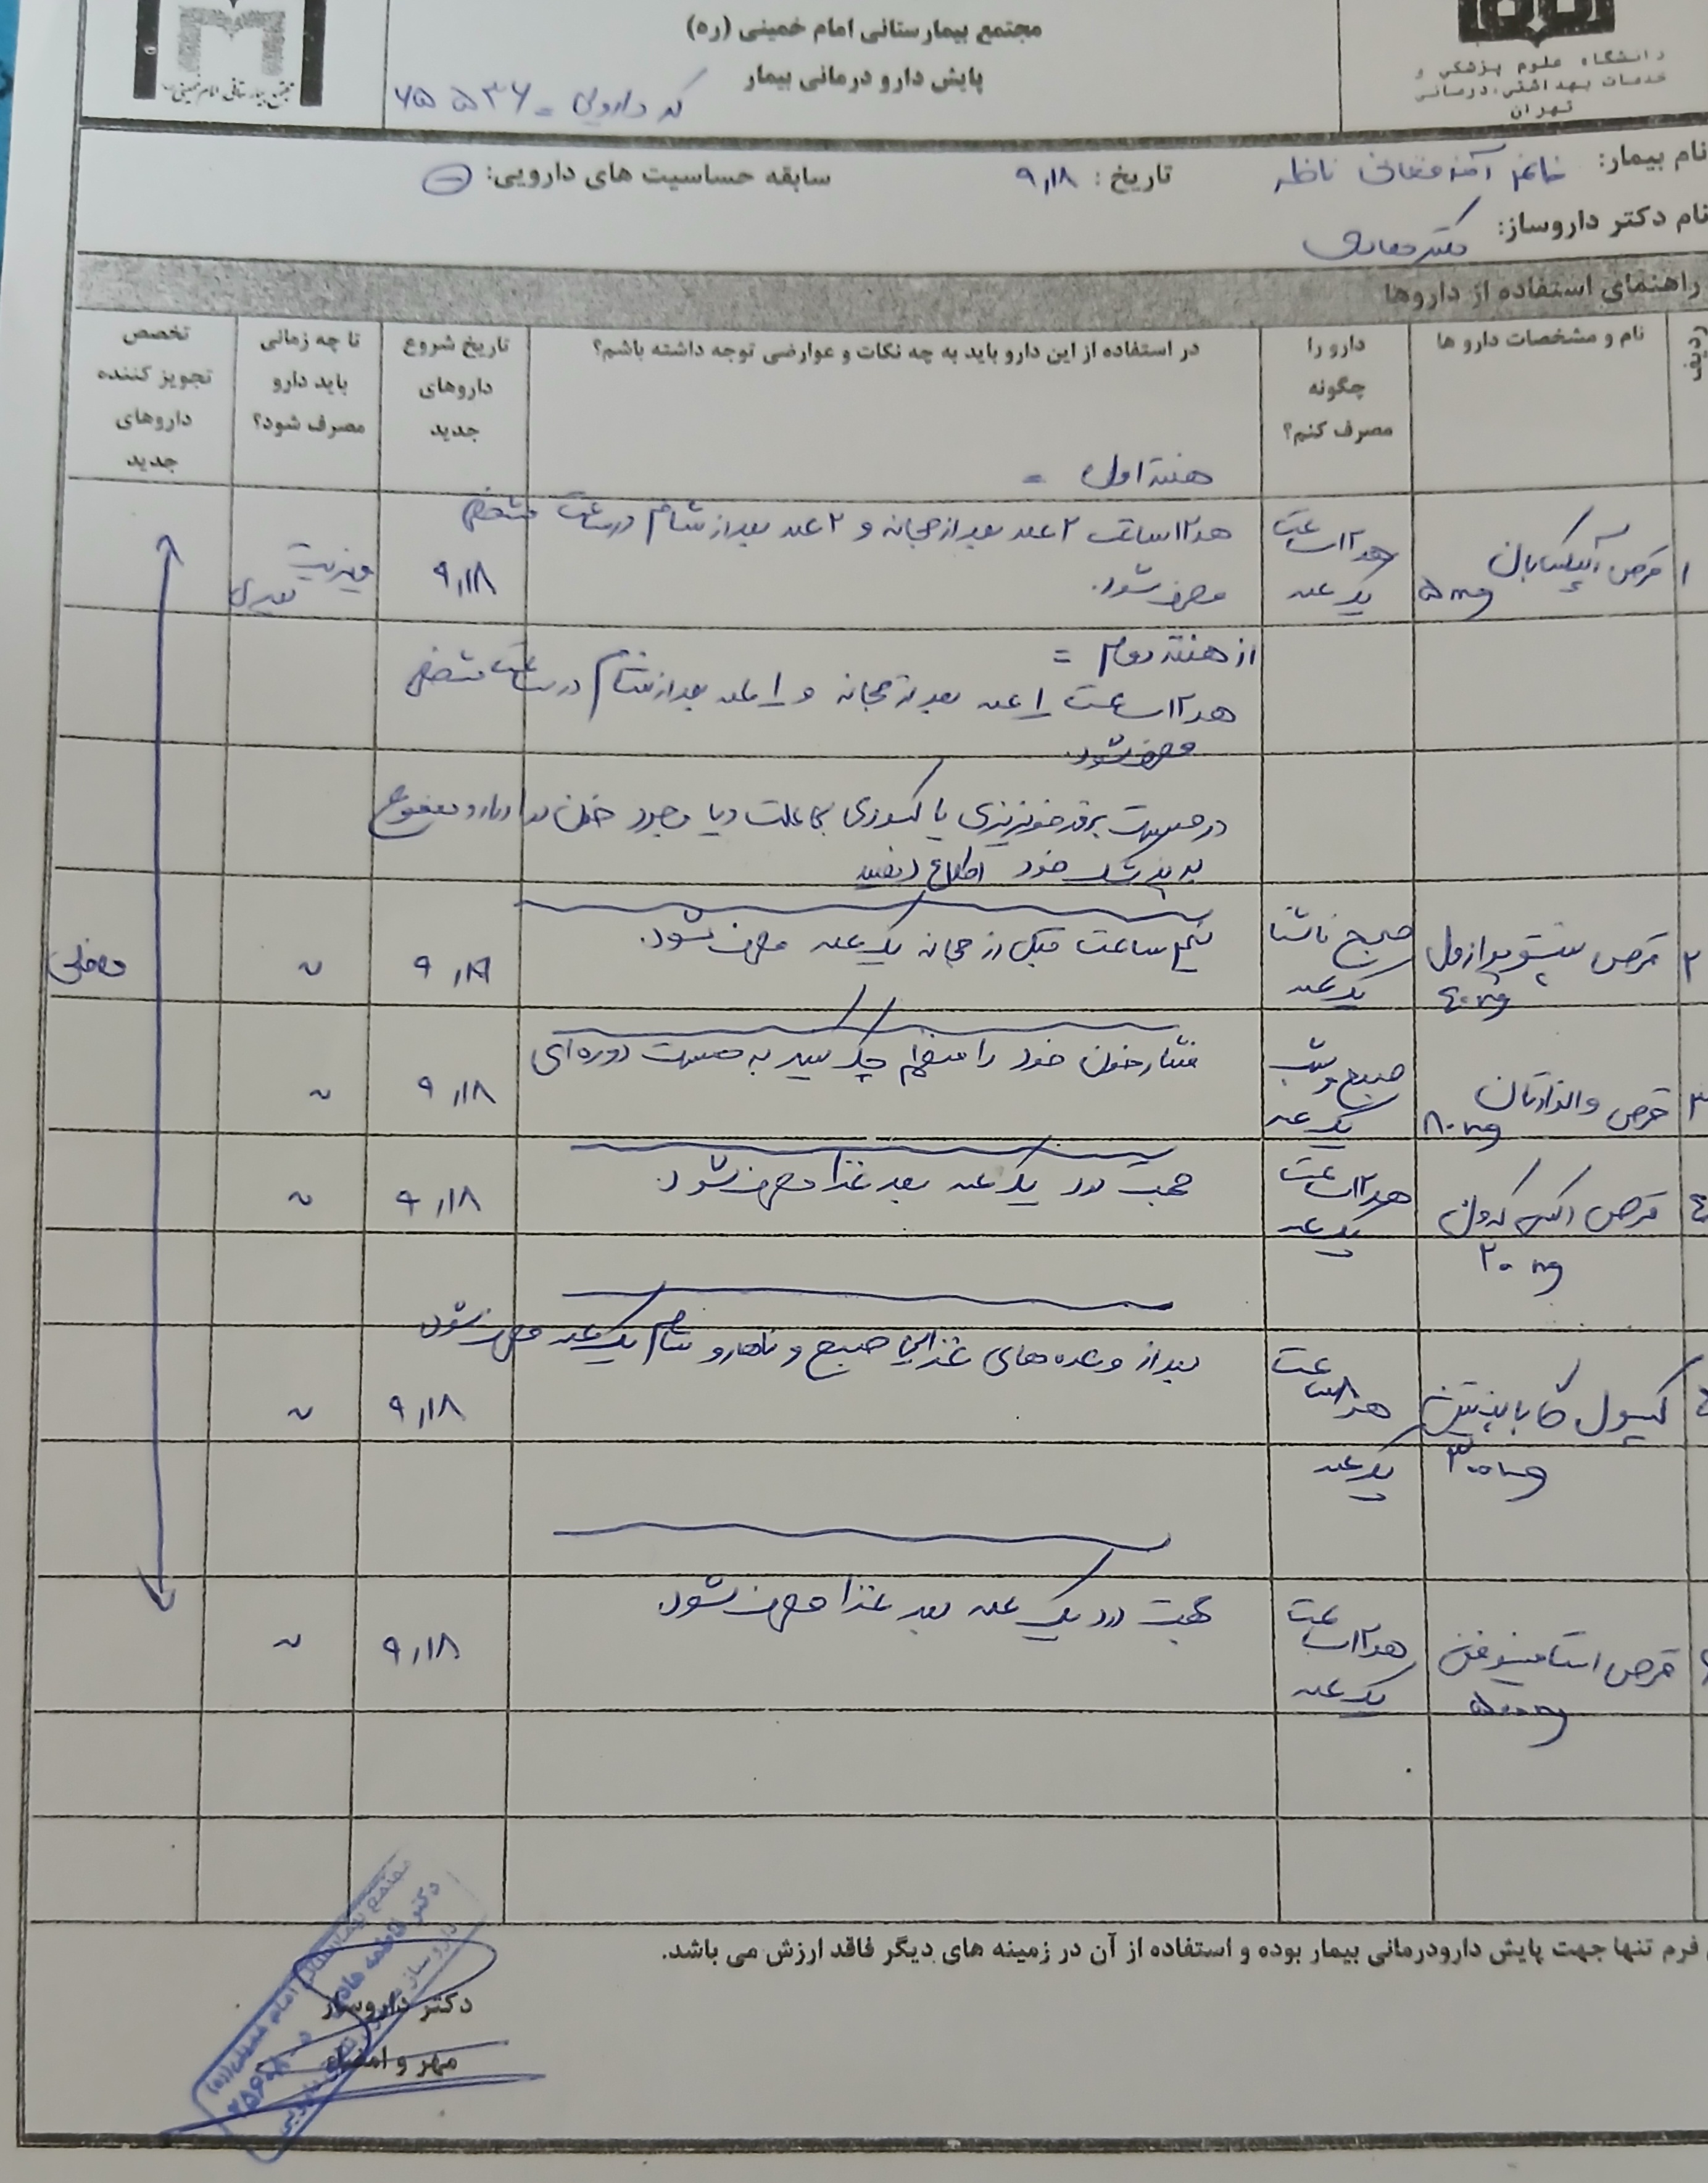

Pentomid 40

Valsartan 80

Apixaban 5

Caltonix 200 I.U.

gabapentin 300

(تصویر مربوط به این مراجعه نیست) Other:

(تصویر مربوط به این مراجعه نیست) Other:

(تصویر مربوط به این مراجعه نیست) Other:

(تصویر مربوط به این مراجعه نیست) Other:

(تصویر مربوط به این مراجعه نیست) Other:

(تصویر مربوط به این مراجعه نیست) Other:

(تصویر مربوط به این مراجعه نیست) Other:

(تصویر مربوط به این مراجعه نیست) Other:

(تصویر مربوط به این مراجعه نیست) Other:

(تصویر مربوط به این مراجعه نیست) Other:

(تصویر مربوط به این مراجعه نیست) Other:

(تصویر مربوط به این مراجعه نیست) Other:

(تصویر مربوط به این مراجعه نیست) Other:

(تصویر مربوط به این مراجعه نیست) Other:

(تصویر مربوط به این مراجعه نیست) Other:

(تصویر مربوط به این مراجعه نیست) Other:

(تصویر مربوط به این مراجعه نیست) Other:

(تصویر مربوط به این مراجعه نیست) Other:

(تصویر مربوط به این مراجعه نیست) Other:

(تصویر مربوط به این مراجعه نیست) Other:

(تصویر مربوط به این مراجعه نیست) Other:

(تصویر مربوط به این مراجعه نیست) Other:

(تصویر مربوط به این مراجعه نیست) Other:

(تصویر مربوط به این مراجعه نیست) Other:

(تصویر مربوط به این مراجعه نیست) Other:

(تصویر مربوط به این مراجعه نیست) Other:

(تصویر مربوط به این مراجعه نیست) Other:

(تصویر مربوط به این مراجعه نیست) Other:

(تصویر مربوط به این مراجعه نیست) Other:

(تصویر مربوط به این مراجعه نیست) Other:

(تصویر مربوط به این مراجعه نیست) Other:

(تصویر مربوط به این مراجعه نیست) Other:

(تصویر مربوط به این مراجعه نیست) Other:

(تصویر مربوط به این مراجعه نیست) Other:

(تصویر مربوط به این مراجعه نیست) Other:

(تصویر مربوط به این مراجعه نیست) Other:

(تصویر مربوط به این مراجعه نیست) Other:

(تصویر مربوط به این مراجعه نیست) Other:

(تصویر مربوط به این مراجعه نیست) Other:

(تصویر مربوط به این مراجعه نیست) Other:

(تصویر مربوط به این مراجعه نیست) Other:

(تصویر مربوط به این مراجعه نیست) Other:

(تصویر مربوط به این مراجعه نیست) Other:

(تصویر مربوط به این مراجعه نیست) Other:

(تصویر مربوط به این مراجعه نیست) Other:

(تصویر مربوط به این مراجعه نیست) Other:

(تصویر مربوط به این مراجعه نیست) Other: